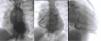

Cateterismo cardíaco diagnóstico.

Ventriculografia esquerda em projeção póstero anterior revela região apical do ventrículo aneurismática, preenchimento da aorta e da artéria coronária direita (A).

Coronariografia direita em projeção póstero anterior e oblíqua anterior direita mostra coronária dilatada que comunica e preenche a artéria coronária esquerda através de rede colateral extensa. O tronco da artéria coronária esquerda origina‐se do tronco da artéria pulmonar. O fluxo de sangue faz‐se: aorta‐> artéria coronária direita‐> colaterais‐> artéria coronária esquerda‐> artéria pulmonar. A porção distal da descendente anterior encontra‐se mal preenchida (B) e (C).